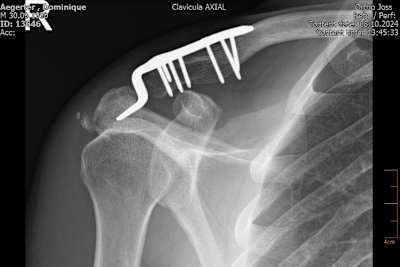

Am Dienstagnachmittag ließ Dominique Aegerter zu Hause in der Schweiz mittels einer Computertomographie neues Bildmaterial anfertigen, um seinen Heilungsfortschritt zu dokumentieren. Der 34-Jährige hat sich bei einem Trainingsunfall mit dem Mountainbike am 28. August auf der rechten Seite vier Rippen gebrochen, dazu das Schlüsselbein; das Schulterblatt und Schulterdach waren angebrochen.